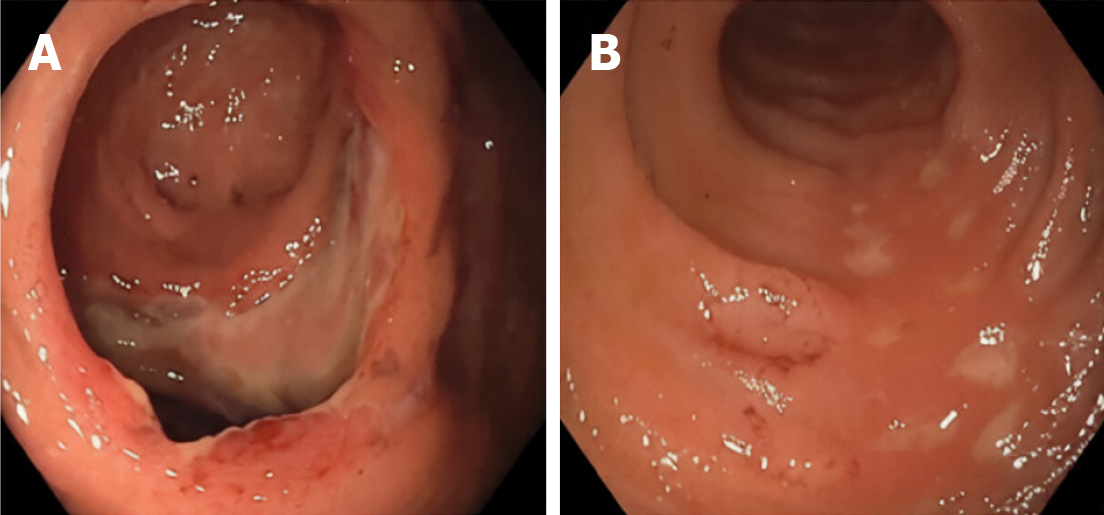

Figure 3 Post-retrieval findings.

A: Localized ulceration at the ileocecal valve corresponding to the impaction site; B: Focal terminal ileal ulceration secondary to prolonged catheter contact, without perforation or active bleeding.